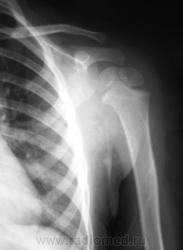

Пол пациента: Мужской пол Тип патологии: Травма Область исследования: Скелетно-мышечная система Методы исследования: Rg Ребенок доставлен по «ургенту». Травма. Направлен на рентгенографию левого плечевого сустава. https://radiomed.ru/sites/default/files/styles/case_slider_image/public/user/12/2.p1190014a.jpg?itok=1gdJVd7R https://radiomed.ru/sites/default/files/styles/case_slider_image/public/user/12/3.p1190015.jpg?itok=J2sCFP2r https://radiomed.ru/sites/default/files/styles/case_slider_image/public/user/12/4.p1190015a.jpg?itok=J9XWCaEU ID:11399 Ср, 19/01/2011 - 17:41 #1 Катенёв Валенти... Не на сайте Был на сайте: 7 лет 2 недели назад Зарегистрирован: 22.03.2008 - 22:15 Публикации: 54876 Для сравнения, дежурный хирург, попросил сделать правый плечевой сустав.Приложения: Ср, 19/01/2011 - 18:50 #2 Vega Не на сайте Был на сайте: 3 месяцев 1 неделя назад Зарегистрирован: 22.01.2009 - 19:16 Публикации: 1087 Перелом левой ключицы Ср, 19/01/2011 - 19:22 #3 Ola-la Не на сайте Был на сайте: 10 месяцев 6 дней назад Зарегистрирован: 06.12.2008 - 09:33 Публикации: 1786 Может быть, если есть клиника, но немного сомнительно. А почему опять нет второй проекции? https://www.instagram.com/pediatricradiology/ Ср, 19/01/2011 - 20:11 #4 Катенёв Валенти... Не на сайте Был на сайте: 7 лет 2 недели назад Зарегистрирован: 22.03.2008 - 22:15 Публикации: 54876 Ola-la wrote: Может быть, если есть клиника, но немного сомнительно. А почему опять нет второй проекции? Ургент! Как дежурный врач требует, так лаборант и делает. Ср, 19/01/2011 - 21:25 #5 Ola-la Не на сайте Был на сайте: 10 месяцев 6 дней назад Зарегистрирован: 06.12.2008 - 09:33 Публикации: 1786 А у нас дежурные требуют всегда в двух проекциях. https://www.instagram.com/pediatricradiology/ Ср, 19/01/2011 - 21:54 #6 Катенёв Валенти... Не на сайте Был на сайте: 7 лет 2 недели назад Зарегистрирован: 22.03.2008 - 22:15 Публикации: 54876 Ola-la wrote: А у нас дежурные требуют всегда в двух проекциях. Сравнили! У Вас, кто дежурит? А, у нас кто? Ваши, что-то хоть сделают, а наши в основном наблюдают...с определенного расстояния.

Для сравнения, дежурный хирург, попросил сделать правый плечевой сустав.